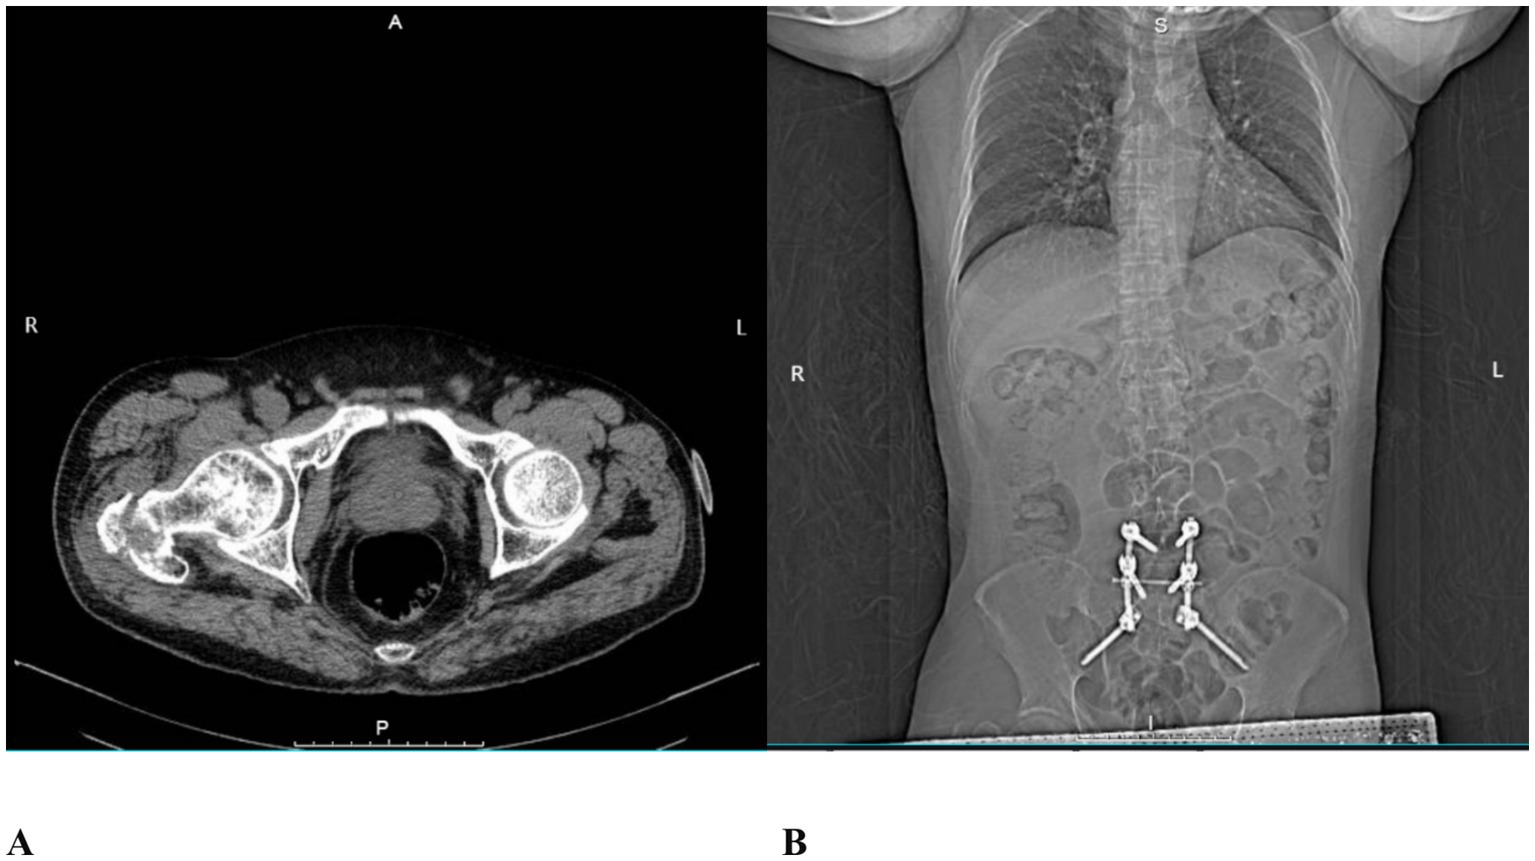

A 64-year-old male patient (165 cm, 75 kg) was admitted to the hospital with right hip pain and restricted mobility following a fall. Computed tomography (CT) revealed a basal fracture of the right femoral neck (Figure 1A).

Figure 1

CT images. (A) Basal fracture of the right femoral neck; (B) Postoperative imaging following prior posterior L5/S1 lumbar interbody fusion.

In 2021, the patient had undergone posterior lumbar interbody fusion for L5/S1 spondylolisthesis (Figure 1B). Postoperatively, he developed failed back surgery syndrome (FBSS) due to unsuccessful fusion, presenting with persistent pain in the L4 to S1 region. His visual analogue scale (VAS) pain scores ranged from 8 to 10 (on a scale where 0 indicates no pain and 10 represents the worst imaginable pain). Persistent lumbosacral pain resulted in a functionally constrained posture, which led to limited hip joint mobility and difficulty with ambulation. The patient reported that this abnormal posture was a significant contributing factor to his recent fall. Due to FBSS-related chronic pain, he required long-term oral administration of tramadol hydrochloride (100 mg per dose, 3–4 times daily) and the application of transdermal fentanyl patches to maintain his VAS pain score at 5. His medical history includes hypertension for 8 years, type 2 diabetes mellitus for 12 years, and coronary artery disease for 7 years. These conditions have been managed with regular oral medications, including nifedipine, metformin, atorvastatin, and aspirin. The patient had no relevant family history of hereditary disease. He had no previous history of urinary retention and no known history of prostatic disease. Prior to the fall, he lived independently.